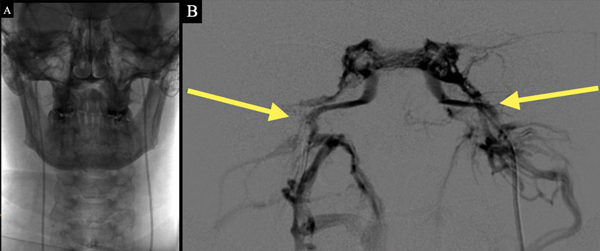

Figura 2. Cateterismo de senos potrosos inferiores. A. Imagen radiológica sin sustracción donde se visualizan ambos catéteres en posición simultáneamente. B. Imagen con sustracción donde se constata correcto posicionamiento de catéteres y tinción de ambos senos petrosos inferiores.

De los 40 pacientes, en 39 (97,5%) se halló lesión hipofisaria en la RM, 20 (50%) fueron microadenomas, 19 (47,5%) macroadenomas y 1 (2,5%) caso con RM negativa para tumor hipofisario. El tamaño promedio fue de 14,2 mm (rango 2-42 mm). En 7 pacientes con microadenoma < a 6 mm y en el único sin imagen visible en RM se realizó CSPI, obteniéndose gradiente central/periférico positivo en todos los casos, en 6 de ellos con lateralización, la cual fue congruente con la imagen y el hallazgo intraoperatorio. Siete (17,5%) adenomas presentaron invasión del seno cavernoso (Knosp 3 y 4). En el paciente con RM negativa se encontró un microadenoma en la cirugía. (Tabla 2)